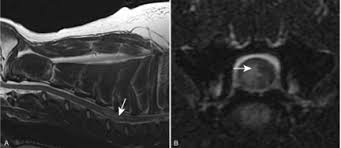

Diagnosis depends on the history and clinical signs, and on ruling out other diseases that can cause similar signs (e.g., disc herniations, spinal fractures). MRI may reveal areas of fluid swelling (edema) within the spinal cord in the first few hours after FCE occurs. Spontaneous recovery also can increase the suspicion of FCE rather than other spinal cord diseases.